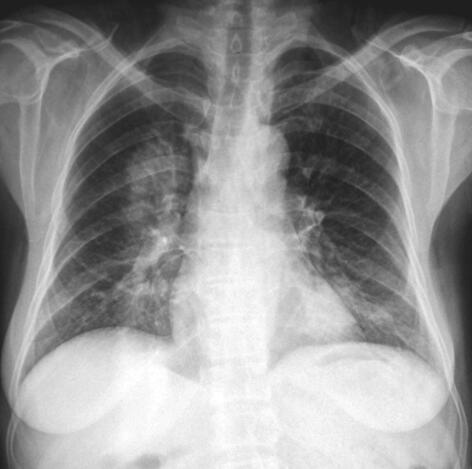

患者,女,52岁,新疆巴楚县农民,维吾尔族。因“间断发热6个月,发现肺部阴影和眼部肿物2个月”于2012年4月10日收入院。患者于6个月前出现间断发热,体温39~40.5℃,伴畏寒、寒战,持续30分钟至3小时可自行降至正常,发热时间间隔2~10天,曾于当地医院行胸片检查“未见明显异常”,给予“头孢类”抗生素治疗无效。2个月前出现双眼不适、右眼视力下降,眼科检查示“右眼肿物”,切除肿物病理示“少许坏死组织”。术前胸片检查发现“右肺上野圆形密度增高影”(图1);肺CT示“右肺上叶团块影,周围见分叶征,内见空洞;左肺下叶球形占位影,周围散在片状渗出影”(图2),遂于当地医院住院诊治。行支气管镜检查发现“右上叶肿物生长,各分支管腔狭窄,右中、下叶各支通畅;左支气管各支通畅”。行左下叶支气管刷检,病理报告“大片炎性渗出及坏死组织”。进而就左肺下叶病变行经皮肺穿刺活检术,病理报告“部分肺泡上皮增生,变性坏死组织炎性细胞浸润”。发热及肺部肿物诊断未明。患者因眼部肿物切除后出现右眼发红、疼痛、视力下降,10天前于我院眼科就诊,诊断为“右眼角膜穿孔、右眼眶蜂窝织炎”,行右眼摘除术,眼球病理示“中性粒细胞浸润,部分组织坏死伴脓性渗出物”。术后5天出现消化道大出血,肠镜示“结肠多发溃疡”,肠黏膜病理示“慢性炎症”,给予输血、止血治疗后出血停止。因发热和肺部肿物原因不明,为进一步诊治收入我科。近1个月患者发热呈持续性,体温39~40℃。10天前眼科术前复查胸片显示“右上叶不张”(图3);肺CT发现“右肺上叶阻塞性肺不张,左肺团块影,周围见片状渗出影”(图4)。患者发病以来,食欲不振、乏力明显,近半年体重下降5kg。

图1 胸片:右肺上野圆形密度增高影